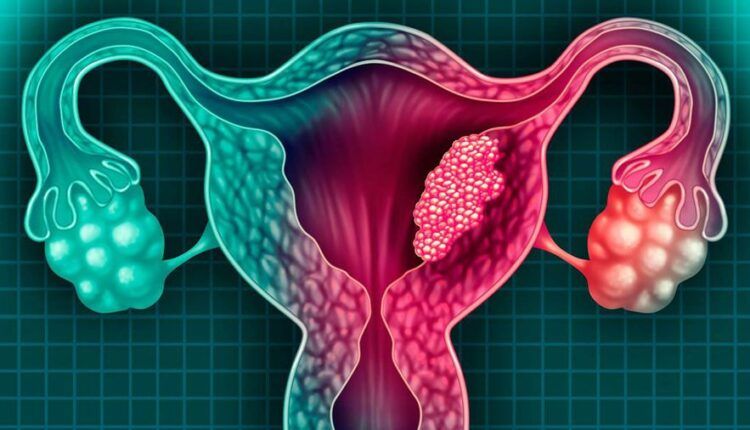

El cáncer cervicouterino se desarrolla cada vez más en mujeres de menor edad. “Antes considerábamos que las de 40 años o más iban a presentar cáncer invasor, y ahora lo estamos teniendo en alrededor de 50 por ciento de los casos, entre las de 25 a 35 años”, alerta Gilberto Nicolás Solorza Luna, académico de la División de Estudios de Posgrado, en la subespecialidad de Ginecología Oncológica, de la Facultad de Medicina (FM) de la UNAM.

Al continuar, Nicolás Solorza Luna, también médico cirujano oncólogo en el Instituto Nacional de Cancerología (INCan), considera que la presencia de este padecimiento podría deberse al inicio de la vida sexual a más temprana edad y con múltiples compañeros sexuales; “eso, combinado, podría estar dando como resultado que el cáncer cervicouterino se esté dando en esas edades”.

Ahora las mujeres asisten a la atención médica con tumores o cáncer de cuello uterino más avanzado. “La sobrevivencia de las pacientes depende del estadio o fase, en el cual se presentan a los tratamientos”, precisa.

Las etapas clínicas de esta enfermedad, explica, van de la I (1) a la IV (4). Por ejemplo, en la IB, cuando el tumor está localizado específicamente en el cuello uterino, la sobrevida es de hasta 90 por ciento; pero si ya avanzó a la fase IIB, ese porcentaje disminuye a 60 por ciento.

Solorza Luna recuerda que este padecimiento es causado por el virus de papiloma humano (VPH) que se propaga a través del contacto sexual con una persona infectada; y cuando la mujer tiene múltiples parejas sexuales se expone también a diversas infecciones.